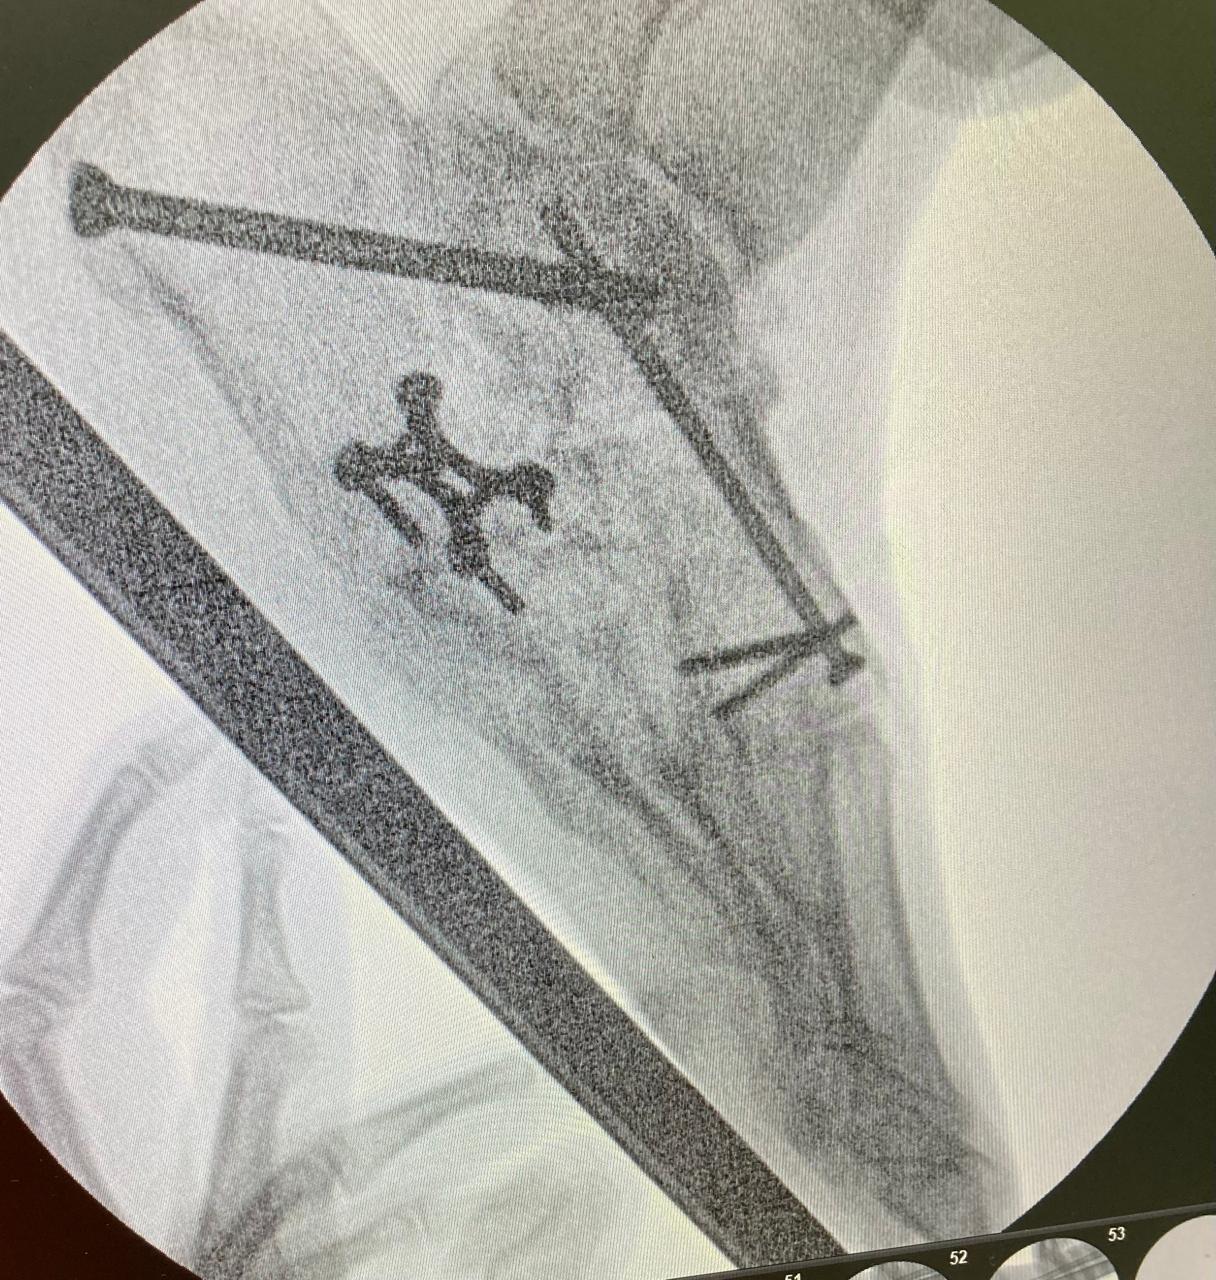

Artropatia diabetica